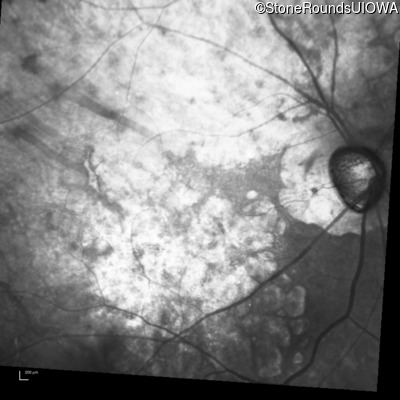

Infrared Fundus Photograph - Right - 20/25 -1

Exemplar